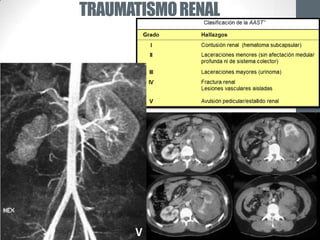

TRAUMATISMO RENAL

IV          II

V